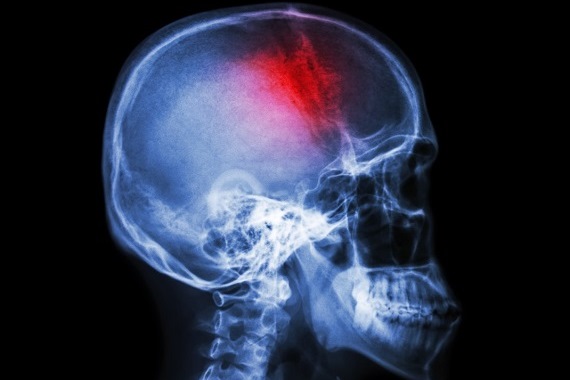

A subarachnoid haemorrhage is a type of haemorrhagic stroke caused by bleeding on the surface of the brain. It is often caused by the bursting of a brain aneurysm. This is a ballooning of a brain blood vessel caused by a weakness in the blood vessel wall. Subarachnoid haemorrhage can be fatal, and people who survive can be left with long-term problems. This is mainly because bleeding on the brain surface triggers spasm of other brain blood vessels, restricting the blood supply and causing additional brain damage.